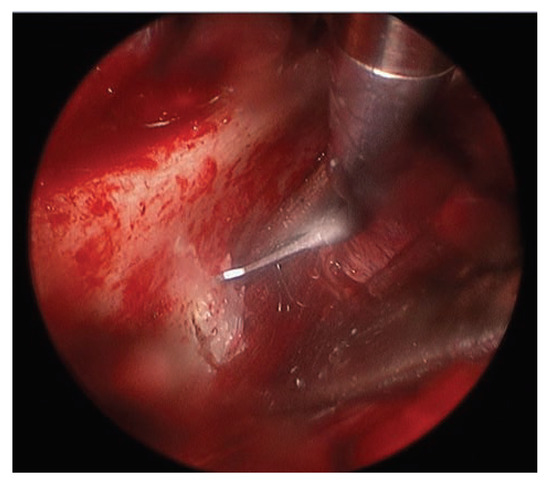

Report of a Case

![]() |